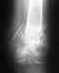

В 2009 году попал под легковую машину,сломало на правой ноге тазобедреную кость чуть выше колена и левую голеностопную кость.

Наложили на ноги апарат Елизарова,год проходил на левой ноге сняли,на правой апарат был 2 года и колено было без движения так как мешала конструкция.Сняли апарат и примерно через полгода кости повело и они начали смещатся.Поставили титановую пластину,всё срослось сняли недели 3 назад.Нашол массажиста,она делает общий массаж тела,но с концентрацией на неразгибающейся ноге.на массажиста костоправа нет денег.Колено сгибается немного.Посоетовайте пожалуйста как самому можно разработать ногу.Спасибо большое заранее.